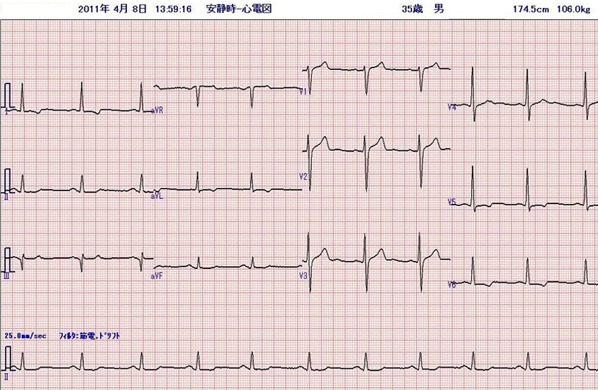

心電図

問題の心電図は洞頻脈、V1で典型的な左房負荷の所見を認め、左室の電位は高く、左室誘導(I、aVL、V5−6)でsagging型のST低下とT波の逆転を認める。典型的な圧負荷に対する左室肥大の所見である。左房負荷の存在から長期間の圧負荷と左心不全の存在が示唆される。来院時の身体所見は、血圧が高く頻脈。心臓では3音、4音がsummation gallopとして聴取されている。急性左心不全による肺水腫の状態である。胸部X線では、心陰影は拡大、左室の拡大と肺血管の再分布を認める。